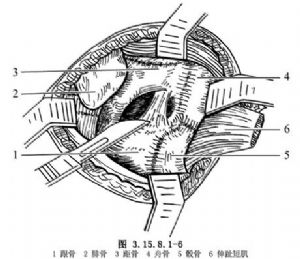

切开皮肤、筋膜组织,不要做皮下浅层分离,防止皮肤坏死。沿切口方向切开踝前十字韧带(图3.15.8.1-4),切口下方的腓骨长短肌腱向下牵拉,将伸趾短肌自跟骨前外侧起点剥离,向远侧翻转,显露跗骨窦,其内有脂肪组织是距跟关节标志(图3.15.8.1-5),清除后切断跟距间韧带,显露距(下)跟关节(图3.15.8.1-6)。在切口上方向前拉开伸趾长肌,在跟骨前即跟骰关节,距骨远端即距舟关节,切开关节囊,足内翻、内收,三个关节都能清楚显露(图3.15.8.1-7)。